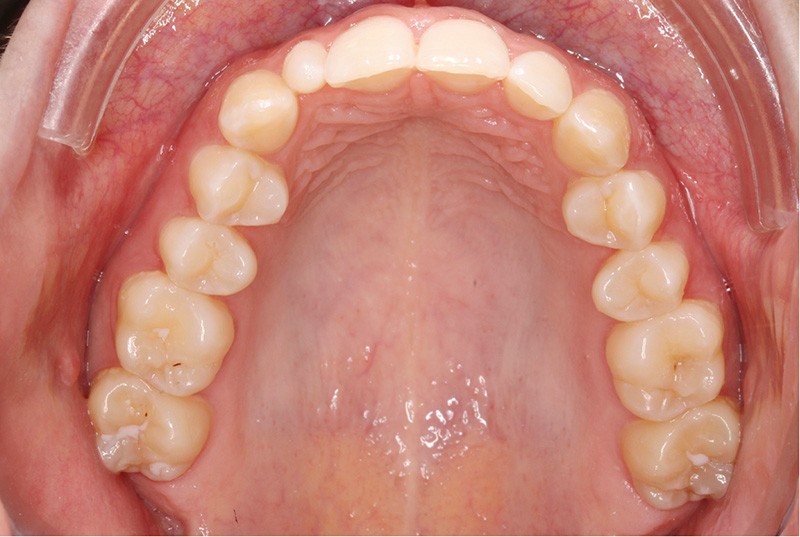

Elle présente une classe I dentaire en denture adulte. Son sourire est perturbé, notamment par la microdontie de son incisive latérale maxillaire droite (la 12). On constate un encombrement modéré au maxillaire (bimarginotopie mésio-palatine et disto-vestibulaire de 13) et plus marqué à la mandibule (monomarginotopie mésio-vestibulaire de 32 et de 43) (fig. 1-6).

Les milieux inter-incisifs ne sont pas coordonnés, à torts partagés, avec une légère déviation à droite du milieu inter-incisif maxillaire et une déviation plus marquée à gauche du milieu inter-incisif mandibulaire ainsi que du point menton. 32 et 33 présentent une tendance à l’exoclusion.